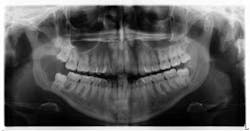

Clinical examination revealed inflamed tissue circa partially erupted No. 32 extending up to the distal of no. 2. The area intraorally was tender to palpation, but unremarkable extraorally. A panoramic X-ray was taken and a large radiolucent lesion was noted to extend from the distal of no. 1 to the distal of no. 32. A significant portion of bone destruction in the mandible was also observed. In addition, a radiolucency was seen distal to the crown on no. 17.

The patient was sent to surgery for enucleation and curettage of the lesion. Differential diagnoses included: unicystic ameloblastoma, odontogenic myxoma, and dentigerous cyst.

Our main concern was the extent of destruction—fracture potential and permanent paresthesia was extremely high. Following surgery, the patient was placed on a liquid diet for six to eight weeks. The specimen was sent to pathology. Diagnosis: dentigerous cyst. Follow-up over the course of the last year has proved to be promising—the bone has filled in, the patient has regained some feeling on the lower right side of her jaw and, thus far, there have been no recurrent or metastatic lesions observed. We are monitoring no. 17 and plan to remove it and the associated radiolucency when the bone has healed sufficiently in the right mandible.